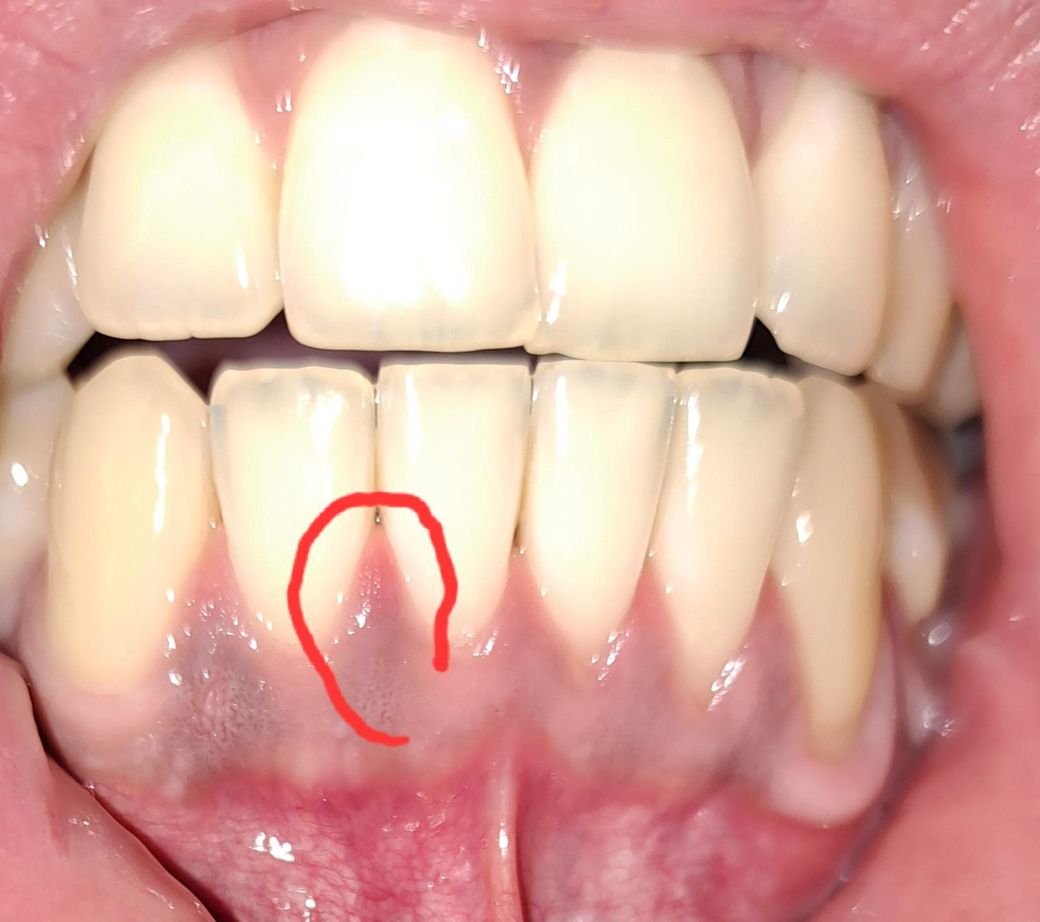

오늘 11시 받고왔고 사진은 새벽 3시 입니다... 오늘 뭐 치료에서 딱히 이상소견이 없었고 마취도 안하고 치근활택술 할정도로 빨리끝났는데 자려고 하다가 보니까 이러네요 ... 플레쉬 터트려서 잘 안보일수도있지만 유독 저기만 끝이 빨간색입니다 ㅠ 왜이럴까요

상처가 생기면서 발적이 나타날 수 있습니다. 치료 받은 후 며칠정도는 불편할 수 있습니다.

사진상으로는 크게 문제가 잇어 보이진 않습니다. 저부위만 약간 잇몸이 부어 잇는거 같으니 양치만 잘해주시면 괜찮을것같습니다.

잇몸치료를 받는 과정에서 일시적으로 잇몸이 자극을받아 1주일정도는 잇몸에 자극감이 남아있어 붉고 출혈이 일부 발생할수 있습니다. 시간이 지나면 좋아지며, 염증이 덧나지 않도록 소독용 가글인 헥사메딘 가글액을 이용하여 가글하여 관리하여 주길 권합니다.